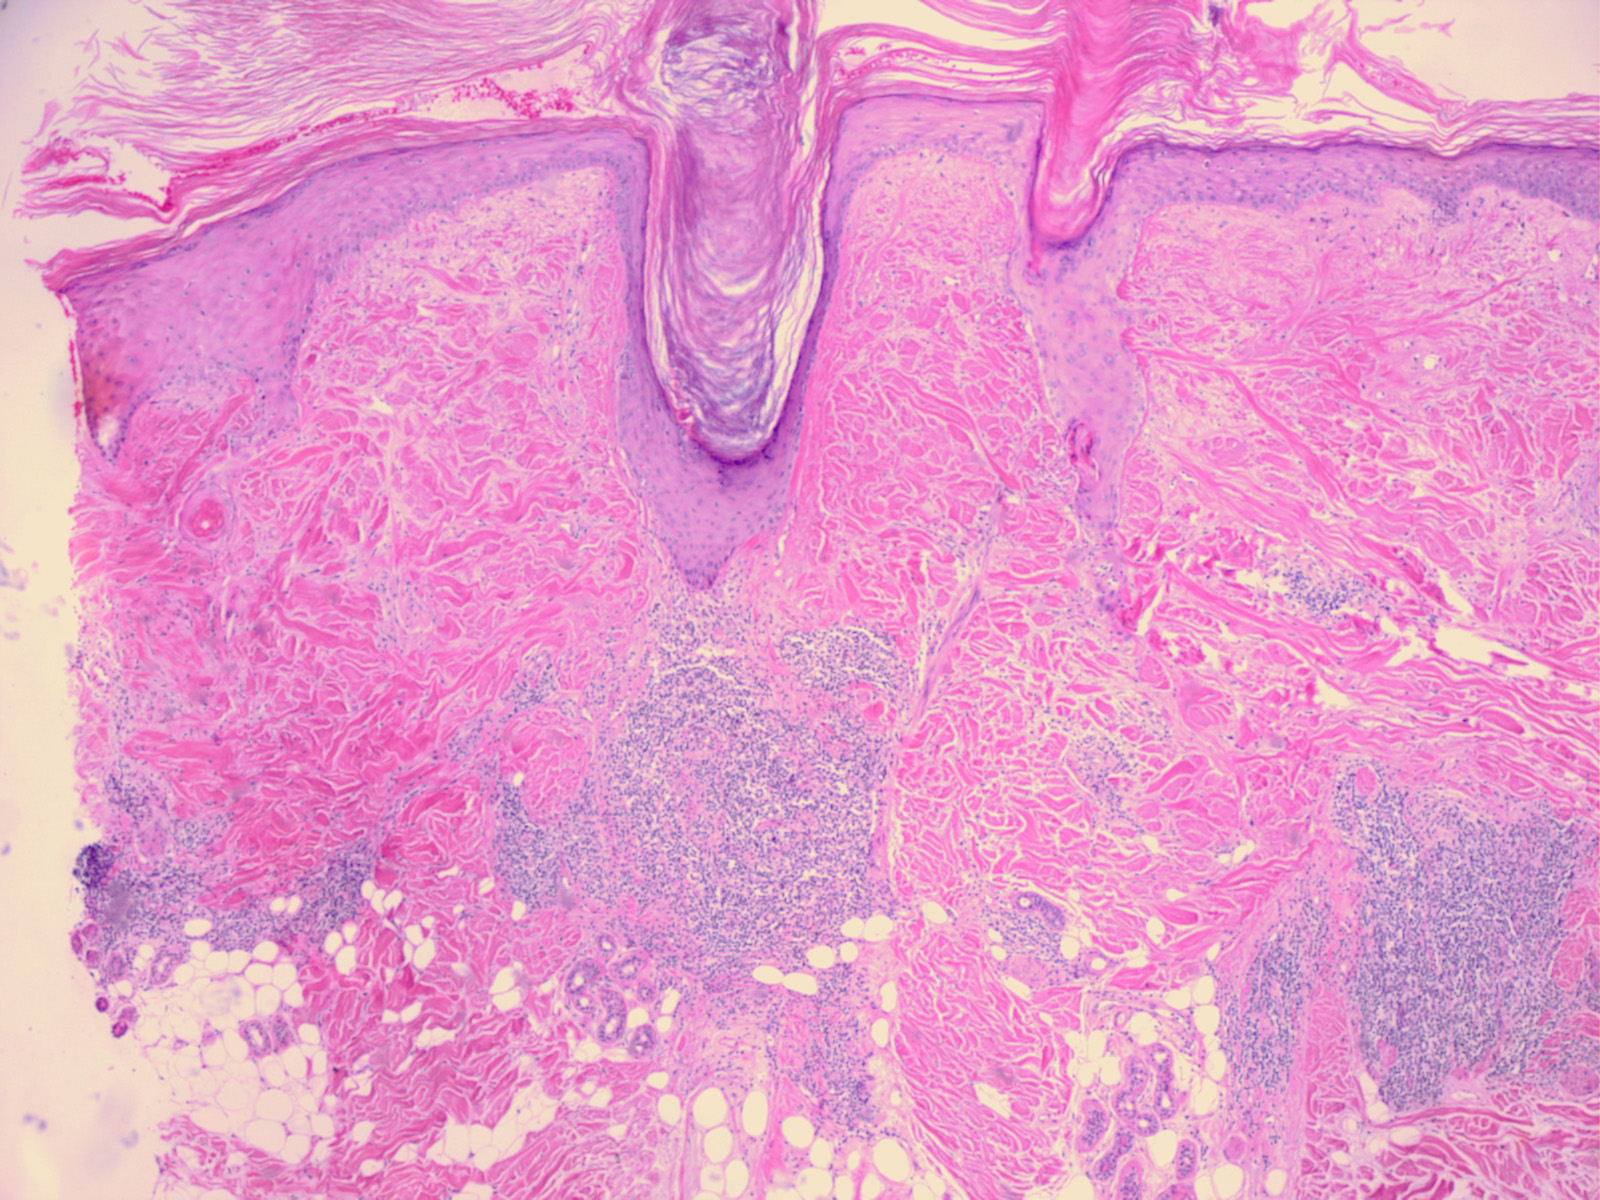

Discoid LE= الذئبة الحمامية القرصية